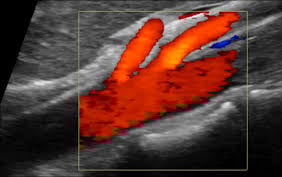

A Mesenteric artery ultrasound, also known as mesenteric duplex, is performed to assess blood flow to the intestines and other abdominal organs. It helps diagnose and monitor conditions like mesenteric artery stenosis (narrowing) or aneurysms. The Doppler ultrasound can measure blood flow velocity in the arteries, helping to identify areas of restricted flow.

Mesenteric arteries are relatively small and located deep within the abdomen, making them challenging to visualize and interrogate with ultrasound. An experienced sonographer is crucial for mesenteric artery ultrasounds due to the technical complexity of imaging these vessels and the need for accurate interpretation of Doppler waveforms. Accurate diagnosis relies on understanding normal and abnormal flow patterns and correctly identifying normal variants, which requires specialized expertise.